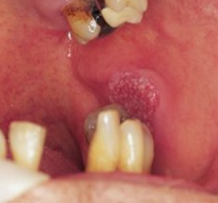

(i) Oral Squamous Cell Carcinoma |

The following clinical photographs indicate some of the more common presentations of oral squamous cell carcinomas. |